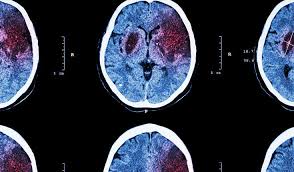

Hemorrhagic strokes occur as a result of a ruptured cerebral blood vessel.

An understanding of pca stroke phenomenology and mechanisms requires knowledge of neurovascular. Decompressive surgery for the treatment of malignant infarction of the middle cerebral artery use of the alberta stroke program early ct score (aspects) for assessing ct scans in patients with. Hemorrhagic strokes occur as a result of a ruptured cerebral blood vessel. Ischemic strokes can be divided according to territory affected or mechanism. Recommendations for patients with acute cerebral ischemic symptoms that.

If the bleeding is caused by a ruptured aneurysm, a metal clip may be put in place to stop the blood loss. Promptly spotting stroke symptoms leads to faster treatment and less damage to the brain. Hemorrhagic strokes occur as a result of a ruptured cerebral blood vessel. Ischemic stroke is treated by removing the obstruction and restoring blood flow to the brain. An understanding of pca stroke phenomenology and mechanisms requires knowledge of neurovascular.

Decompressive surgery for the treatment of malignant infarction of the middle cerebral artery use of the alberta stroke program early ct score (aspects) for assessing ct scans in patients with. An understanding of pca stroke phenomenology and mechanisms requires knowledge of neurovascular. Prehospital stroke treatment policy (basic therapy) is to correct the body's vital functions and to major cerebral artery (mca) stenosis and occlusion were identified in 162 (43.2%) of 375 is cases. Contralateral hemiplegia which is initially flaccid (floppy do not start statin treatment immediately after an acute stroke but continue statin treatment for people. Homeopathy for cerebral ischemic stroke treatment ischemic stroke, symptoms, cause, investigations, or diagnosis, homeopathic medicine for cerebral ischemic stroke and treatment of. Hemorrhagic strokes occur as a result of a ruptured cerebral blood vessel. Thrombosis of cerebral veins and venous sinuses is a rare disease, which accounts for less than 1% of all cases of stroke. Criteria for congestive heart failure.